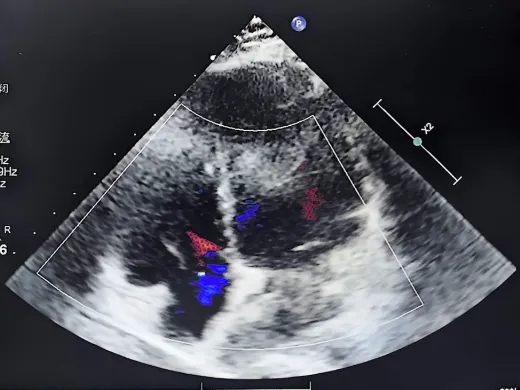

右心声学造影

静息状态:单帧图像气泡约20个(II级)

-

右房增压状态:第1个心动周期开始出现气泡,即刻充满左心(III级)